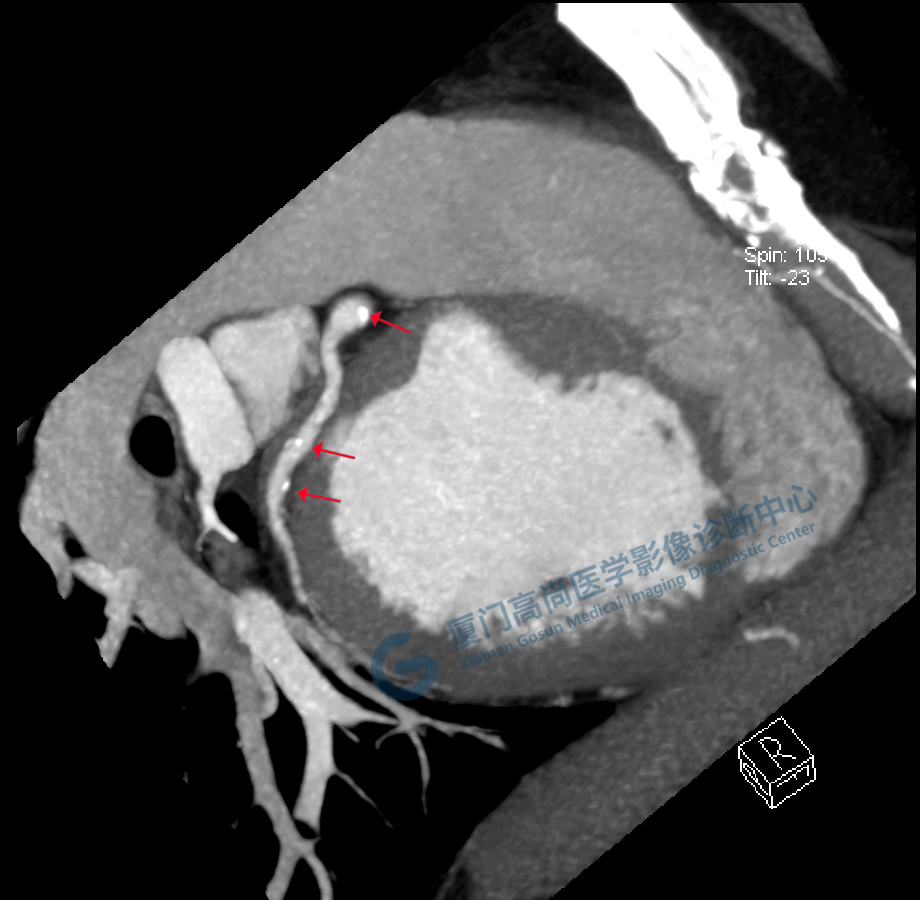

冠脈CTA圖像

左、右冠開(kāi)口

冠狀CTA右冠

回旋支

前降支

圖像所見(jiàn):左冠狀動(dòng)脈前降支,前降支近段可見(jiàn)局部鈣化斑塊,管腔狹窄約5%,左側(cè)冠狀動(dòng)脈對(duì)角支可見(jiàn)鈣化斑塊,管腔狹窄約20%-30%。

左冠狀動(dòng)脈回旋支,近段可見(jiàn)局部鈣化斑塊,管腔狹窄約5%-10%。

影像診斷:CAD-RADS分級(jí):2(25%-49%),輕度狹窄。